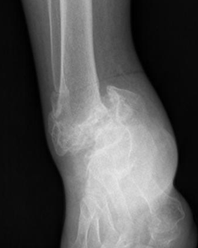

Fig 41. Artropatía neuropática. Patrón hipertrófico.

Rx lateral. Disminución del espacio tibioastragalino, con esclerosis y formación de osteofitos anteriores. Fractura consolidada de la tibia, como desencadenante.